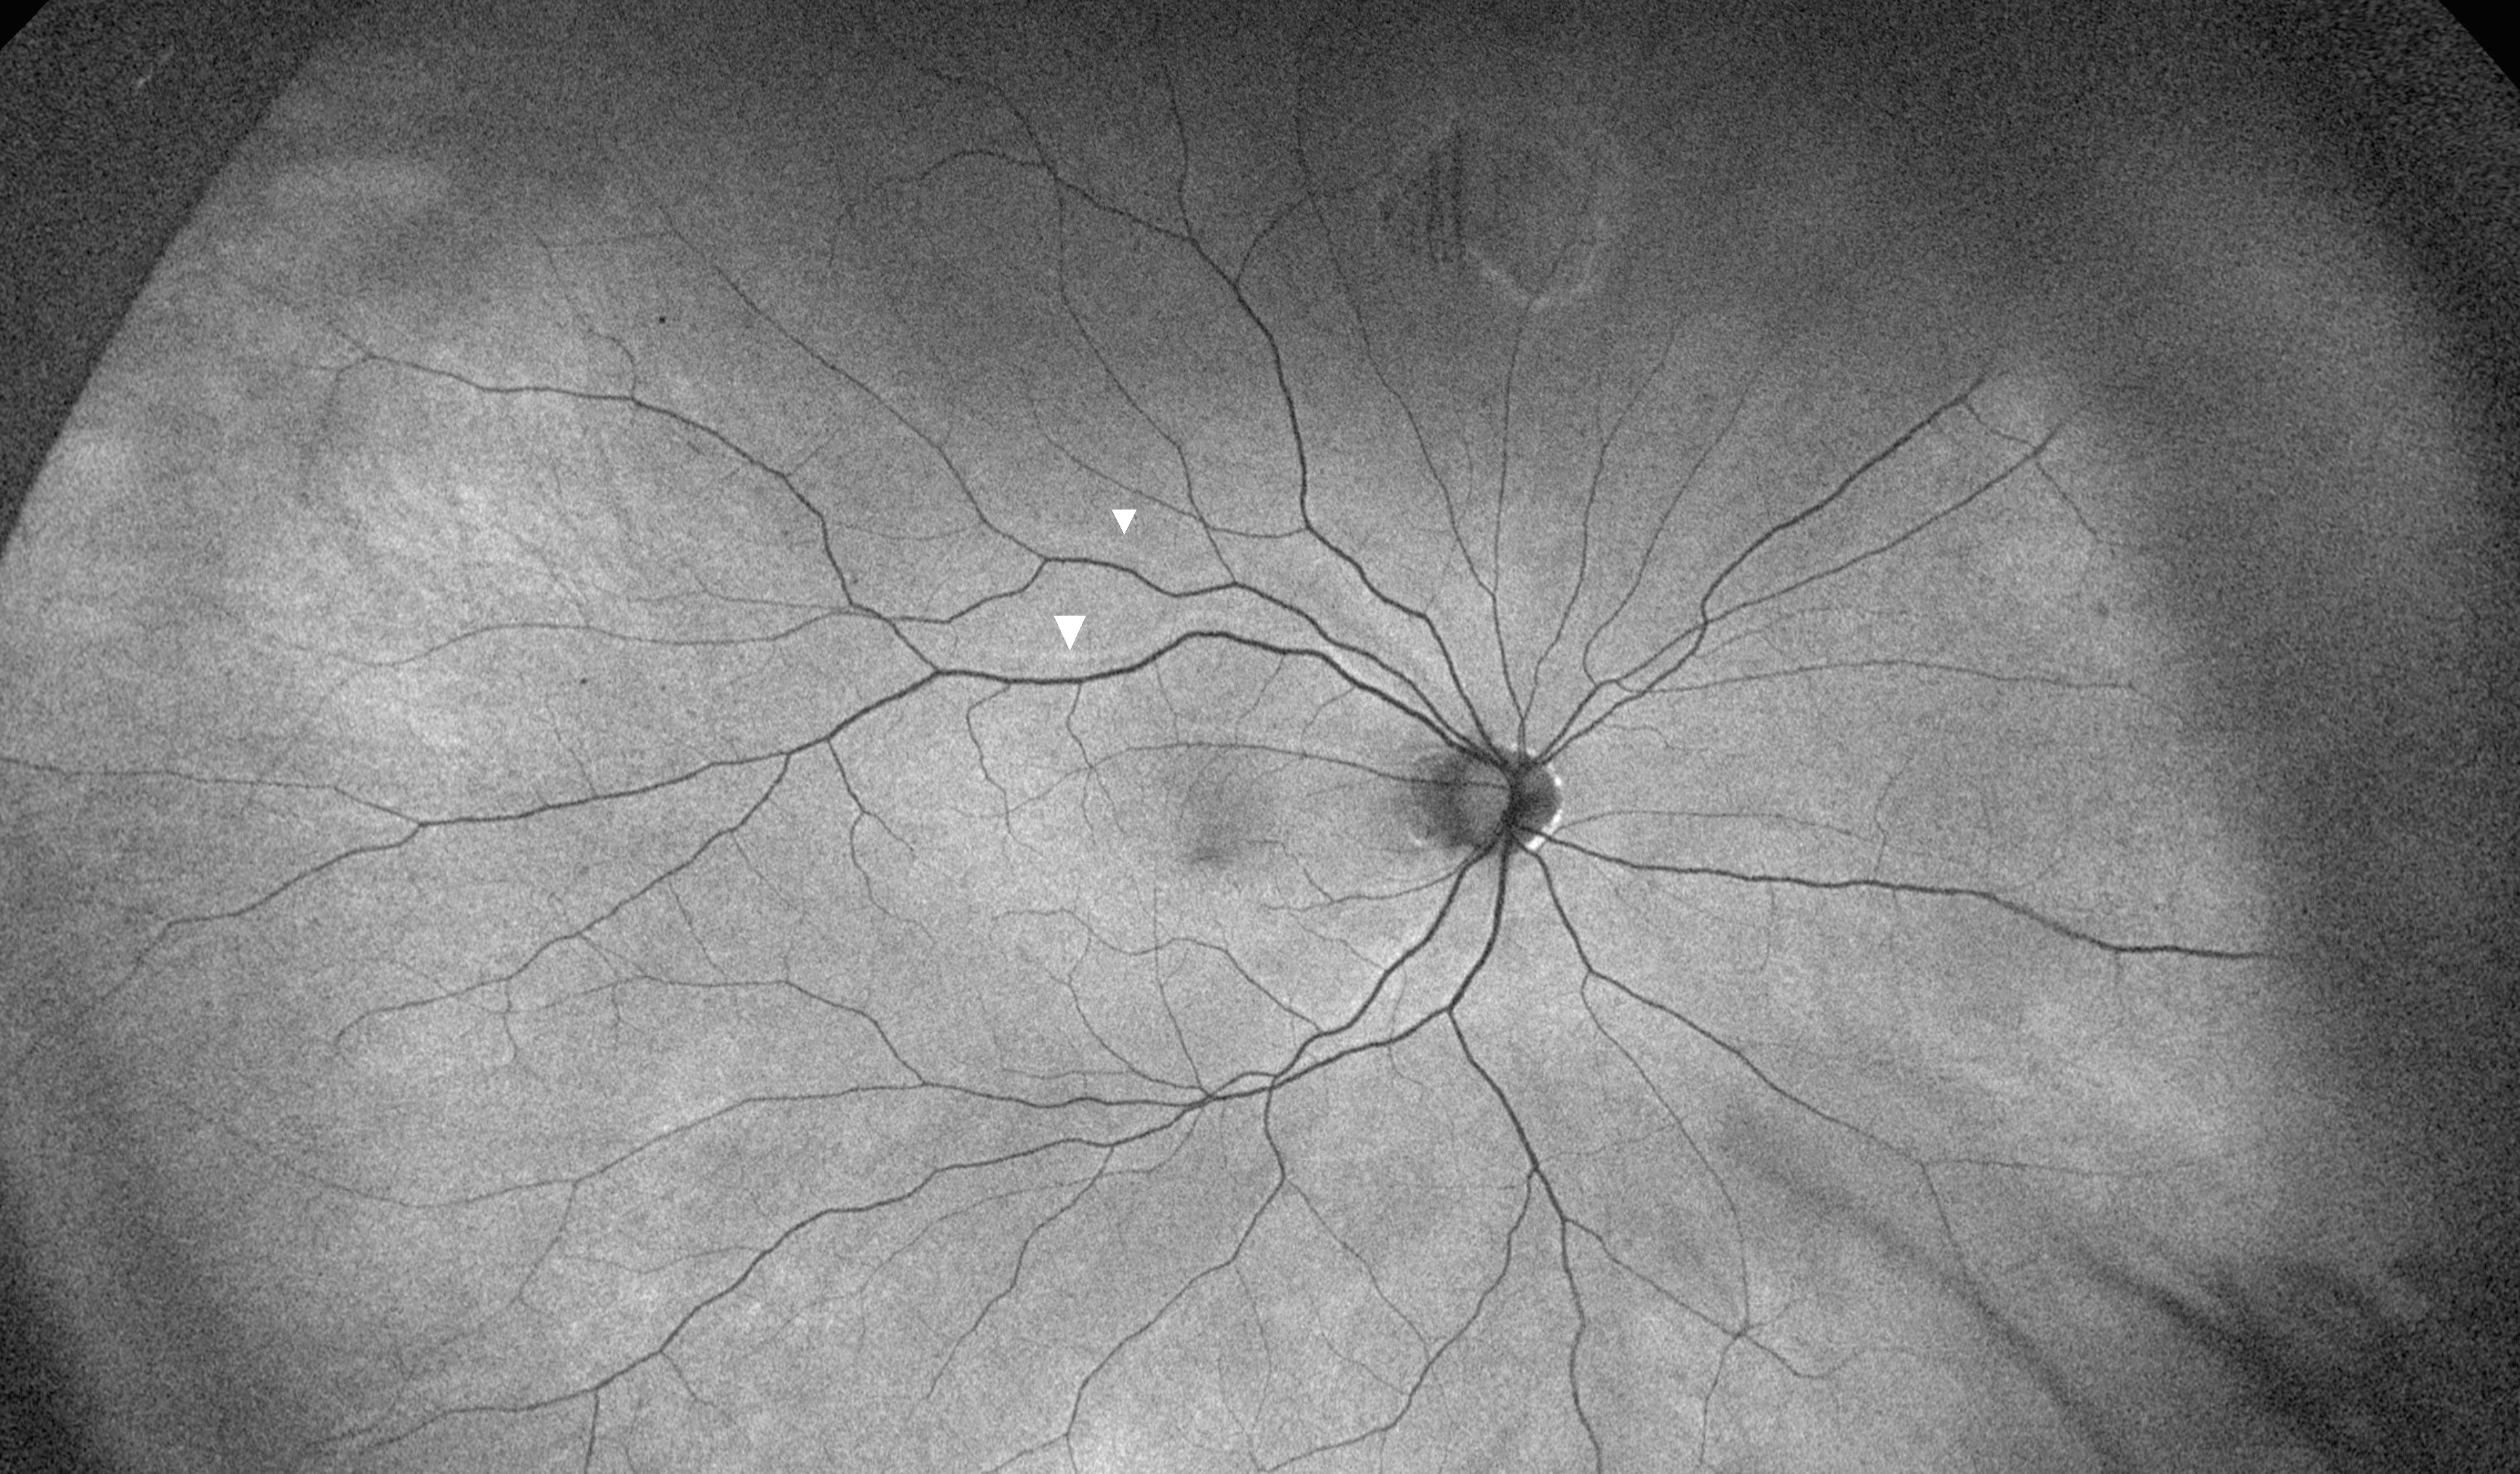

Fundus autofluorescence (FAF) after incisional repair of rhegmatogenous retinal detachment (RRD). FAF showing retinal vessel imprinting and retinal displacement (arrowheads) following pars plana vitrectomy (PPV) with C3F8 tamponade and fluid drainage through superior retinotomy in a patient with macula-off RRD.